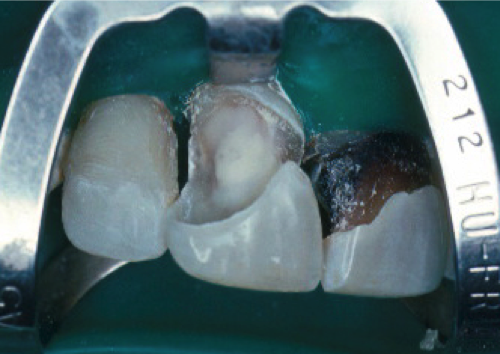

The sectional matrix of dead-soft stainless steel is placed (Figure 9).

Fig 9. Sectional matrix placement.

Figure 9